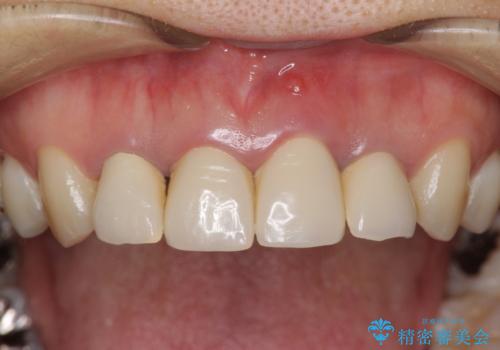

- 歯ぐきの黒っぽさ、暗い色調の前歯の改善を求めて来院されました。

金属のフレームを用いるクラウンは色調が暗くなる傾向にありますが、セラミッククラウンに置き換えたことで自然な明るさ、審美性を取り戻すことができました。